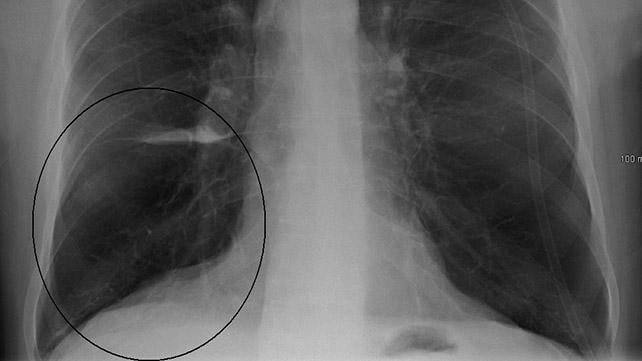

Chụp X-quang lồng ngực hoặc CT

Chụp CT là một kỹ thuật sử dụng tia X để tạo hình ảnh chi tiết hơn so với việc chụp X-quang cổ điển. Bất kỳ phương pháp dùng tia X nào mà bác sĩ lựa chọn đều giúp đưa ra hình ảnh về các cấu trúc bên trong lồng ngực bao gồm tim, phổi và mạch máu.

Bác sĩ dựa vào kết quả hình ảnh để có thể chẩn đoán COPD hoặc xác định các tình trạng bệnh khác, như suy tim, cũng gây ra các triệu chứng tương tự.

Thực hiện chụp X-quang cổ điển hay chụp CT đều không gây đau nhưng bạn sẽ tiếp xúc với một lượng nhỏ tia phóng xạ.

Bức xạ được sử dụng để chụp CT lớn hơn mức cần thiết khi chụp X-quang cổ điển. Mặc dù liều phóng xạ cho mỗi lần xét nghiệm tương đối thấp nhưng cũng góp phần vào lượng phơi nhiễm phóng xạ bạn nhận được trong suốt đời. Điều này có thể làm tăng nhẹ nguy cơ ung thư.

Tuy nhiên, các thiết bị CT mới đã cải tiến với mức bức xạ ít hơn mà vẫn tạo ra hình ảnh chi tiết.